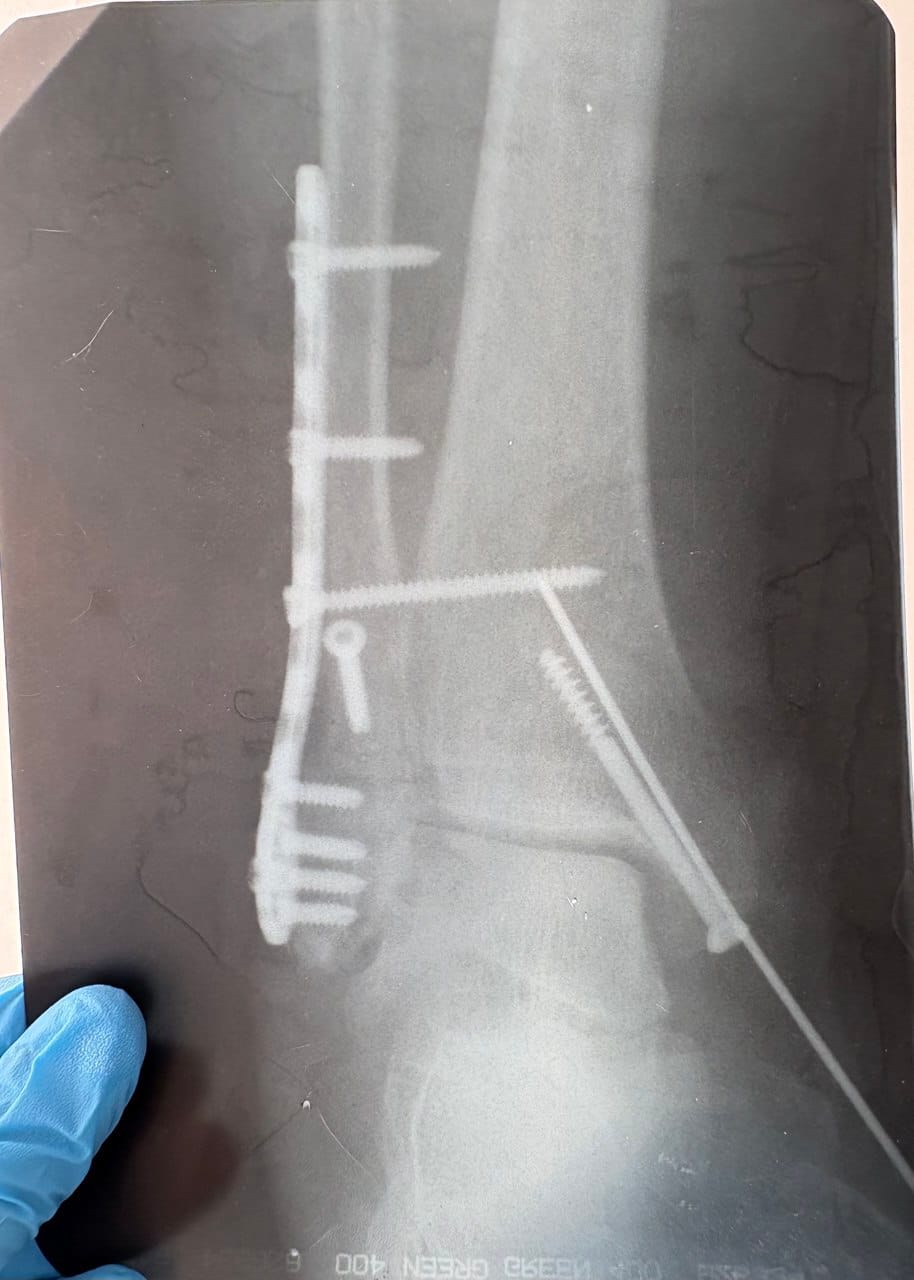

- рентген — для анализа костных структур;

- Ортопедические операции для коррекции костных и суставных деформаций.